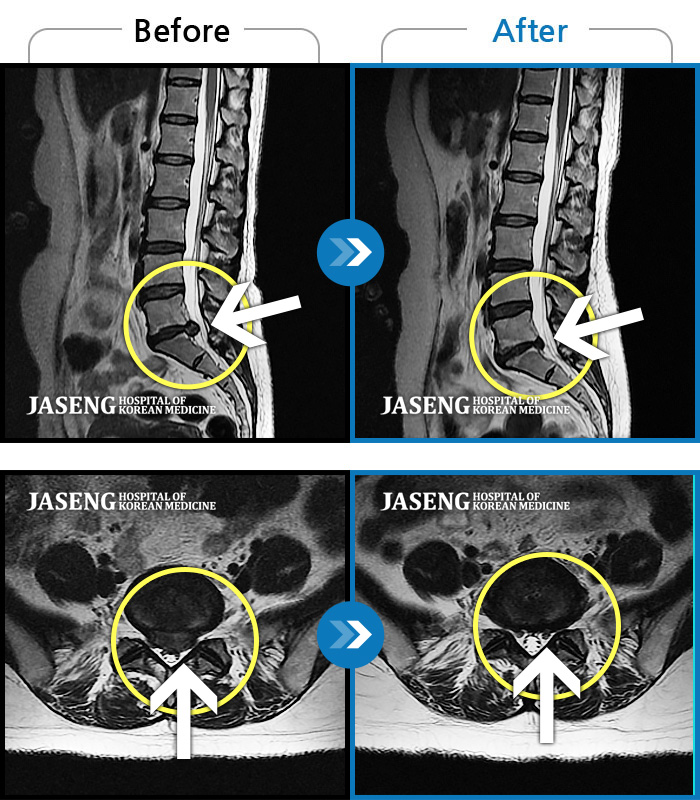

허리디스크

안산 · 김민수 원장

발목의 힘이 떨어져서 절뚝거리면서 걸었다.

촬영시기

2022.01.03 ~ 2024.07.31

2024.08.09

조회수 518